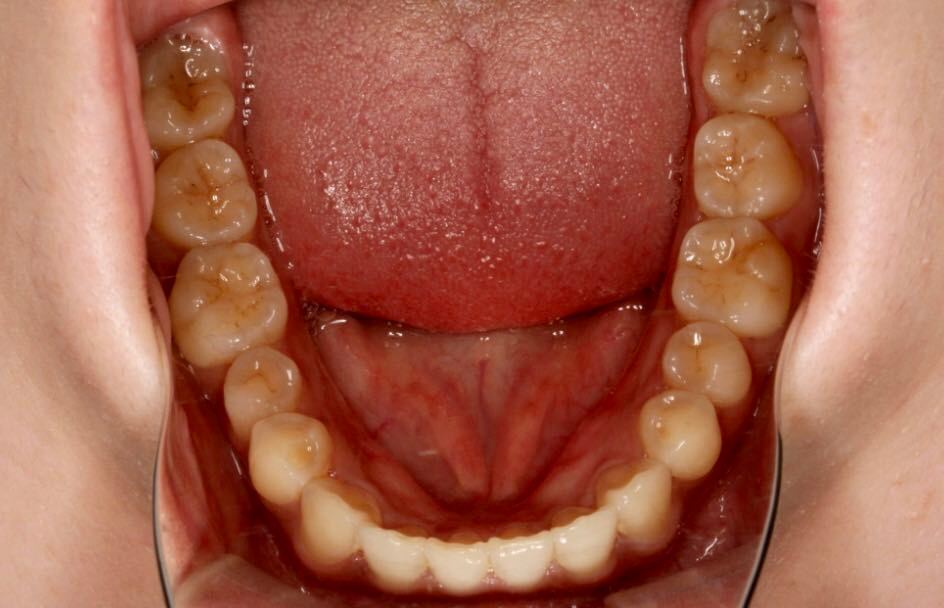

矫正前口内照:

口内:恒牙列,牙列拥挤(中度)。上下颌牙弓呈方圆型。左右对称。右侧磨牙近中性关系,左侧磨牙近中关系,右侧尖牙远中关系,左侧尖牙远牙中性关系。上颌中线偏右2mm,下中性居中。

功能检查:张口度,张口型正常。